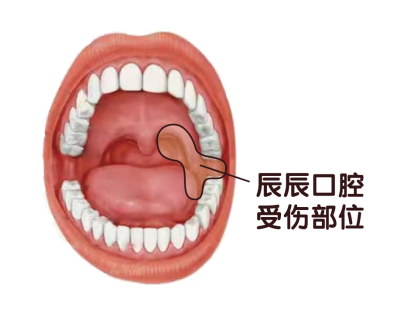

经过口腔科主任李超医生检查,辰辰口腔上腭及舌背部有大量的黑色血痂,口腔内部的不规则裂伤从左侧下颌牙槽嵴顶远中向舌侧至口底,到达软腭的腭舌弓,上面有大量黄色伪膜,存在牙龈裂伤、软腭开放性损伤、软组织感染等问题。虽然玩具箭箭头质地较软,但是箭羽上尖锐的倒勾造成辰辰口腔受伤,为确保辰辰得到全方位地治疗,李超主任带领专业团队紧急为辰辰积极完善术前检查,经过与家长的详细沟通,当天为辰辰进行了全麻下行清创缝合。

“孩子到医院的时候已经开始发烧,血象明显升高,要是第一时间送到这里,孩子也不用受这么多罪,”李超主任提醒家长,“软腭与吞咽、语言有着密切相关,软腭损伤后伤口出血、疼痛、组织的撕裂中断或穿通缺损,直接妨碍患儿的语言和进食,加上因为就诊时间的耽误,孩子伤口污染加重,可能出现继发感染,容易出现愈合慢、疤痕增大的问题,影响孩子的腭部功能。”

口腔和腭部损伤多发于1-6岁儿童,牙刷、铅笔、筷子、棒棒糖、伞把、遥控器等日常用品都有可能造成孩子口腔损伤,家长一定不要让孩子拿着尖锐的东西边走边玩或放入口中,容易玩耍跌倒磕碰出现意外,最严重的会穿过腭部直达颅底。1岁左右的孩子正处于学走路的年龄段,走路不稳,容易摔跤,经常张着嘴走路,极易出现不慎摔倒致使舌头被新萌出的牙咬裂的意外,严重者甚至会将舌头咬断。